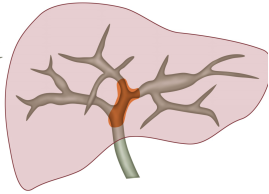

病灶评估:通过计算机辅助手术规划系统进行了三维重建,绿色为胆管系统,黄色为肿瘤病灶,红色为主动脉系统。术前诊断:肝门部胆管癌(IV型)

病情特点:病灶主要位于左右肝管汇合部,偏向左侧。患者存在胆管变异,右前、右后肝管不相通,右前胆管汇入左肝管,B4和左外肝管不相通。

脉管评估:计算机辅助手术规划系统进行三维重建,精确评估脉管空间走行。红色为肝动脉和腹主动脉,蓝色为门静脉系统,绿色为胆管系统。